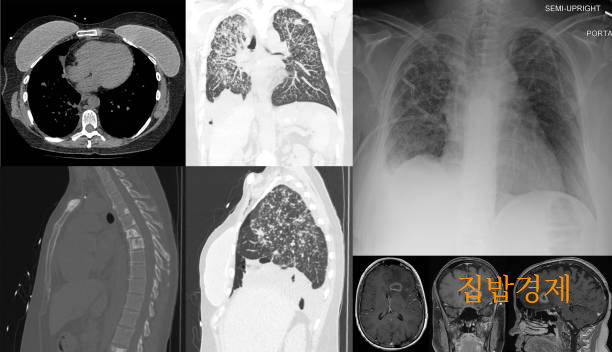

기흉은 폐에 생긴 구멍으로 공기가 새면서 늑막강 안에 비정상적인 공기 축적되어 부피가 증가하고 폐조직에 압력이 생기는 질환이며 새는 공기의 양이 증가할수록 폐가 정상 기능을 하지 못하게 되는데요

흉강 안으로 유입되는 공기가 배출되지 않아 양쪽 폐와 심장 사이의 공간과 심장이 한쪽으로 쏠리며 가슴 통증, 호흡곤란 등 응급 상황이 발생할 수 증상이 나타나면 즉시 응급실에 방문하여 적절한 치료가 필요한 질환이에요